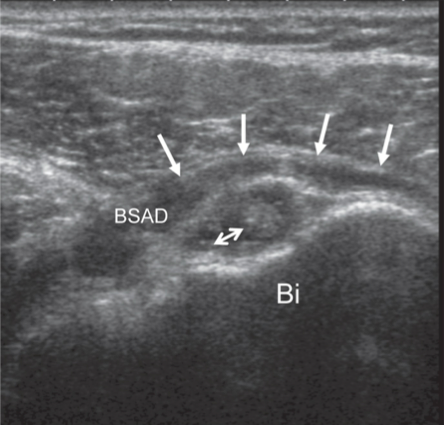

Patient se présente pour une douleur à l’épaule. Que voyez- vous à l’imagerie ?

Signe du double épanchement sur une coupe antérieure axiale passant par la partie basse du long biceps.

Épanchement de la BSAD (flèches simples) et épanchement de la gaine du long biceps (double flèche).

Signe indirect de rupture transfixiante de la coiffe avec une spécificité supérieure à 90 %.